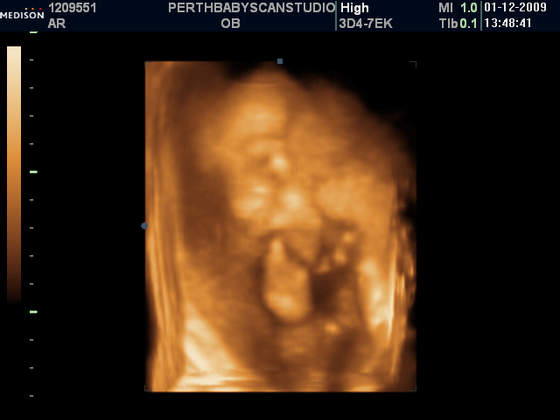

A mi gin w poniedzialek powiedzial, ze Mala wazy ponad 1000g!!! I, ze wg Niego, po wymiarach na usg i wygladu brzuszka, ciaza jest starsza o jakies 2 tyg.